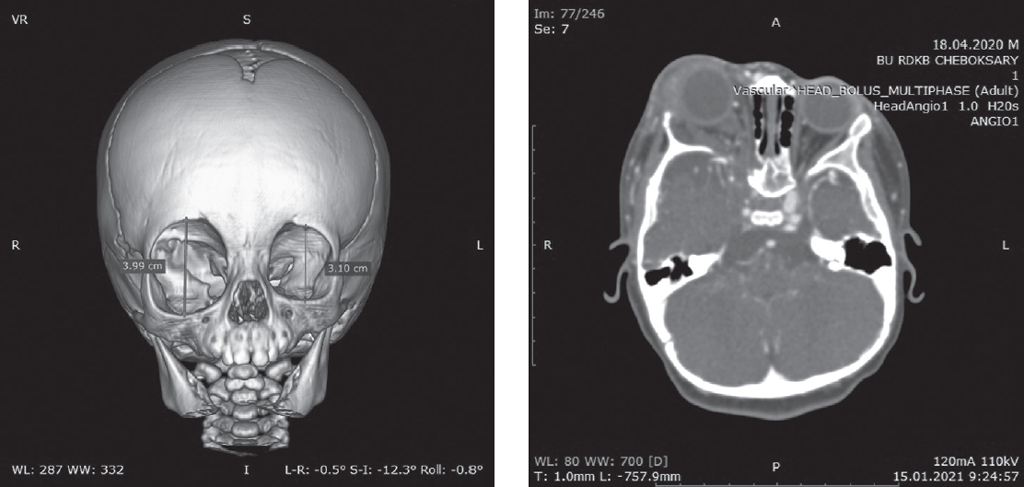

The article describes a clinical case of familial neurofibromatosis type I. This diagnosis was made in a nine-month-old patient according to the diagnostic criteria recommended by the International Expert Committee on Neurofibromatosis. Clinicaly, there were hyperpigmented café-au-lait spot on the skin, the presence of one plexiform neurofibroma, the father had a genetically confirmed diagnosis of neurofibromatosis type I. Also after birth, this patient was diagnosed with buphthalmos.

A mutation in the Neurofibromin gene NFI leads to increased cell proliferation, with a rapidly progressive course, characterized by combined damage to the skin, eyes, nervous system and some internal organs, leading to neuroectodermal and mesodermal dysplasia. Neurofibromin is an intracellular protein in the human genome that regulates several pathways of growth control and plays a key role in the pathogenesis of congenital glaucoma associated with neurofibromatosis type I and plexiform neurofibroma. Plexiform neurofibroma originates from the sheaths of the peripheral nerves, often affects multiple nerves, is abundantly perfused, and is a benign neoplasm, but there is a lifelong risk of malignancy. On the other hand, congenital glaucoma is a relatively rare disease, usually due to infiltration of the anterior chamber angle by neurofibromas, closure of the angle by neurofibromatous-thickened ciliary body and choroid, fibrovascularization. The clinical picture of neurofibromatosis type I can be very variable, even among members of the same family. Under the influence of a combination of pathogenetic factors, an asymptomatic course is determined in one individual, while in another, the disease proceeds in a severe form, up to disability.

Surgical treatment for isolated orbital plexiform neurofibroma is used to decompress the orbit and prevent malignancy of the tumor. It should be noted that due to the peculiarity of the structure of the tumor, its total removal is often not possible. In this case, mini-frontal access was used.

After the intervention, exophthalmos regressed, ophthalmotonus returned to normal. The child was discharged in a satisfactory condition.

Thus, the described clinical case is of particular interest, based on the combination of orbital plexiform neurofibroma and congenital glaucoma associated with neurofibromatosis type I.